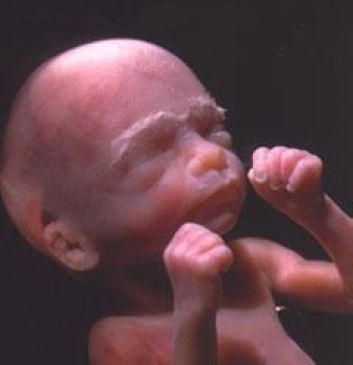

третій місяць

9-10-й тиждень . Уже розвинулася печінку, з'явилися бруньки і сеча починає виливатися в амніотичну рідину. Ясно помітно особа, адже голова випросталася і стає більше схожа на «людську»

Очі, що знаходилися далеко з боків голови, знаходяться тепер на обличчі, вони прикриті віями. Змальовані губи, але вуха ще схожі на щілинки. Кінцівки стають довшими.

11-12-й тиждень. Сформовано перші кістки. Плід почав рухатися, але так слабо, що мама ще не може цього виявити. За допомогою ультразвукового стетоскопа батьки можуть почути серцебиття майбутньої дитини. Протягом цього місяця диференціюються статеві органи